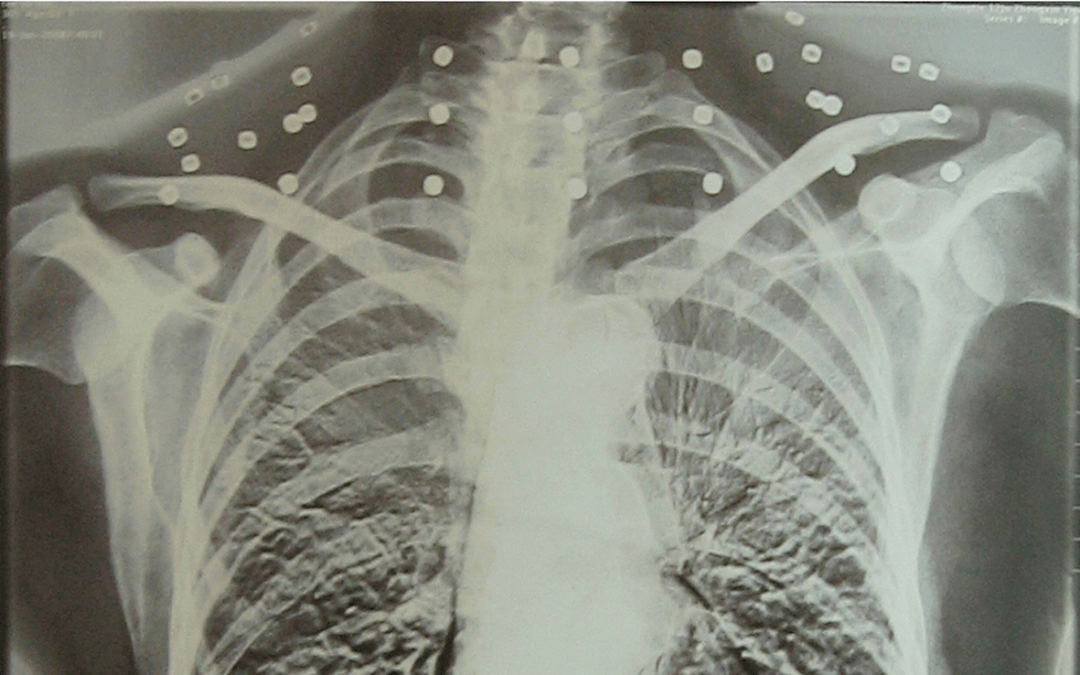

这张照片

是今年82岁的吴以先老人

拍摄的一张CT照

但实际上是

吴以先的颈部和腹部

共分布着33枚弹片

但是打进身体里的弹片

一直留在了体内

他体内的弹片都没有取出

但吴以先不考虑取出弹片

在他看来

这是他与战友并肩作战的见证

是他的勋章

岁月虽逝,硝烟散去

但那份军人的荣耀与担当

与吴以先身上那33枚弹片

一起永远烙印在他心中

33枚“军功章”

是一名军人的光荣

也是一位英雄的至诚本色